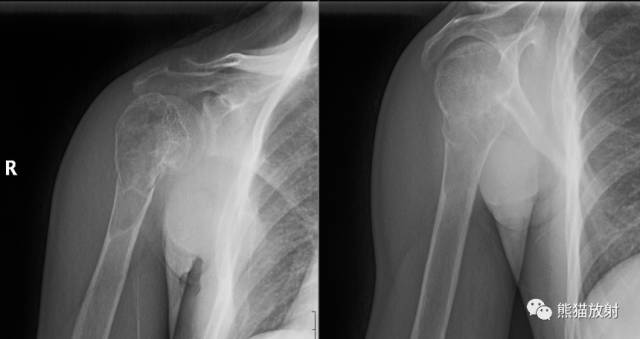

II型及III型 ↓ 肱骨上段Ewing肉瘤(男7岁)